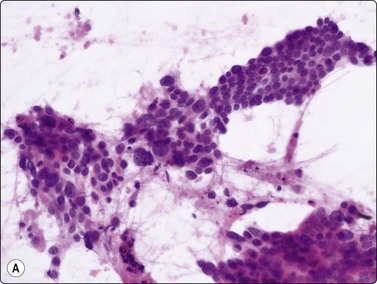

image image

Fig. 11.18 Islet cell tumor

(A) Poorly cohesive sheets and dispersal; cells with oval nuclei, stippled chromatin and small nucleoli (Pap, IP); (B) Mainly dispersed cells with uniformly round nuclei, speckled chromatin, moderate anisokaryosis; delicate cytoplasm; a suggestion of pseudorosettes (MGG, HP).

Criteria for diagnosis

Many single and loosely grouped cells, pseudorosettes,

Rounded monotonous nuclei, mild to moderate anisokaryosis,

Speckled chromatin and 1–3 small nucleoli,

Poorly defined, finely granular cytoplasm, often dispersed in the background,

Nuclei eccentric if cytoplasm intact.

These functional or nonfunctioning tumors of adults are situated mainly in the body and tail of the pancreas. The tumors are well within the scope of EUS cytodiagnosis.114,115 The neoplastic cells are mainly dissociated, but often form loose acinar or follicular clusters and curved or circular rows (Fig. 11.18). In the majority of cases, nuclei are characteristically round to oval and uniformly small. Occasionally, nuclear anisokaryosis may be prominent, but the nuclear chromatin pattern varies little between cells. The chromatin is evenly distributed, coarsely granular or ‘speckled’. The small nucleoli are not easily seen in Giemsa-stained smears. Due to its fragility, the cytoplasm is often dispersed in the background. When it is preserved, nuclei are eccentrically situated within defined cell borders. A very fine, red granularity is often discernible in MGG smears with high magnification. Clumps of amyloid may occasionally be seen, but necrosis is not observed.113,116-119 The cytological pattern of most islet cell tumors is sufficiently characteristic to be easily distinguished from that of pancreatic adenocarcinoma. Production and secretion of specific hormone products cannot be distinguished on the basis of routine cytological smears alone. If the secretory products of the neoplastic cells can be identified by immunocytochemical methods, a more specific diagnosis can be made with confidence. General neuroendocrine markers will usually be positive, such as neuron-specific enolase, synaptophysin, chromogranin-A, PGP9.5 and CD56. Specific secretory products, e.g. insulin can be marked by appropriate antibodies but this does not necessarily correlate with raised serum levels. Electron microscopy will demonstrate dense-core neurosecretory granules. A decision on whether a tumor is benign or malignant is problematic. Even histopathology is poorly predictive of aggressive behavior. In general, nuclear atypia and pleomorphism cannot be relied on as cytological criteria of malignancy (Fig. 11.20). More aggressive behavior correlates with a raised proliferation index assessed using Ki-67 immunohistochemistry (> 2%).120 This is a parameter in the WHO 2004 histology based-grading system.121,122 Only documentation of metastasis finally provides proof of malignancy.123,124